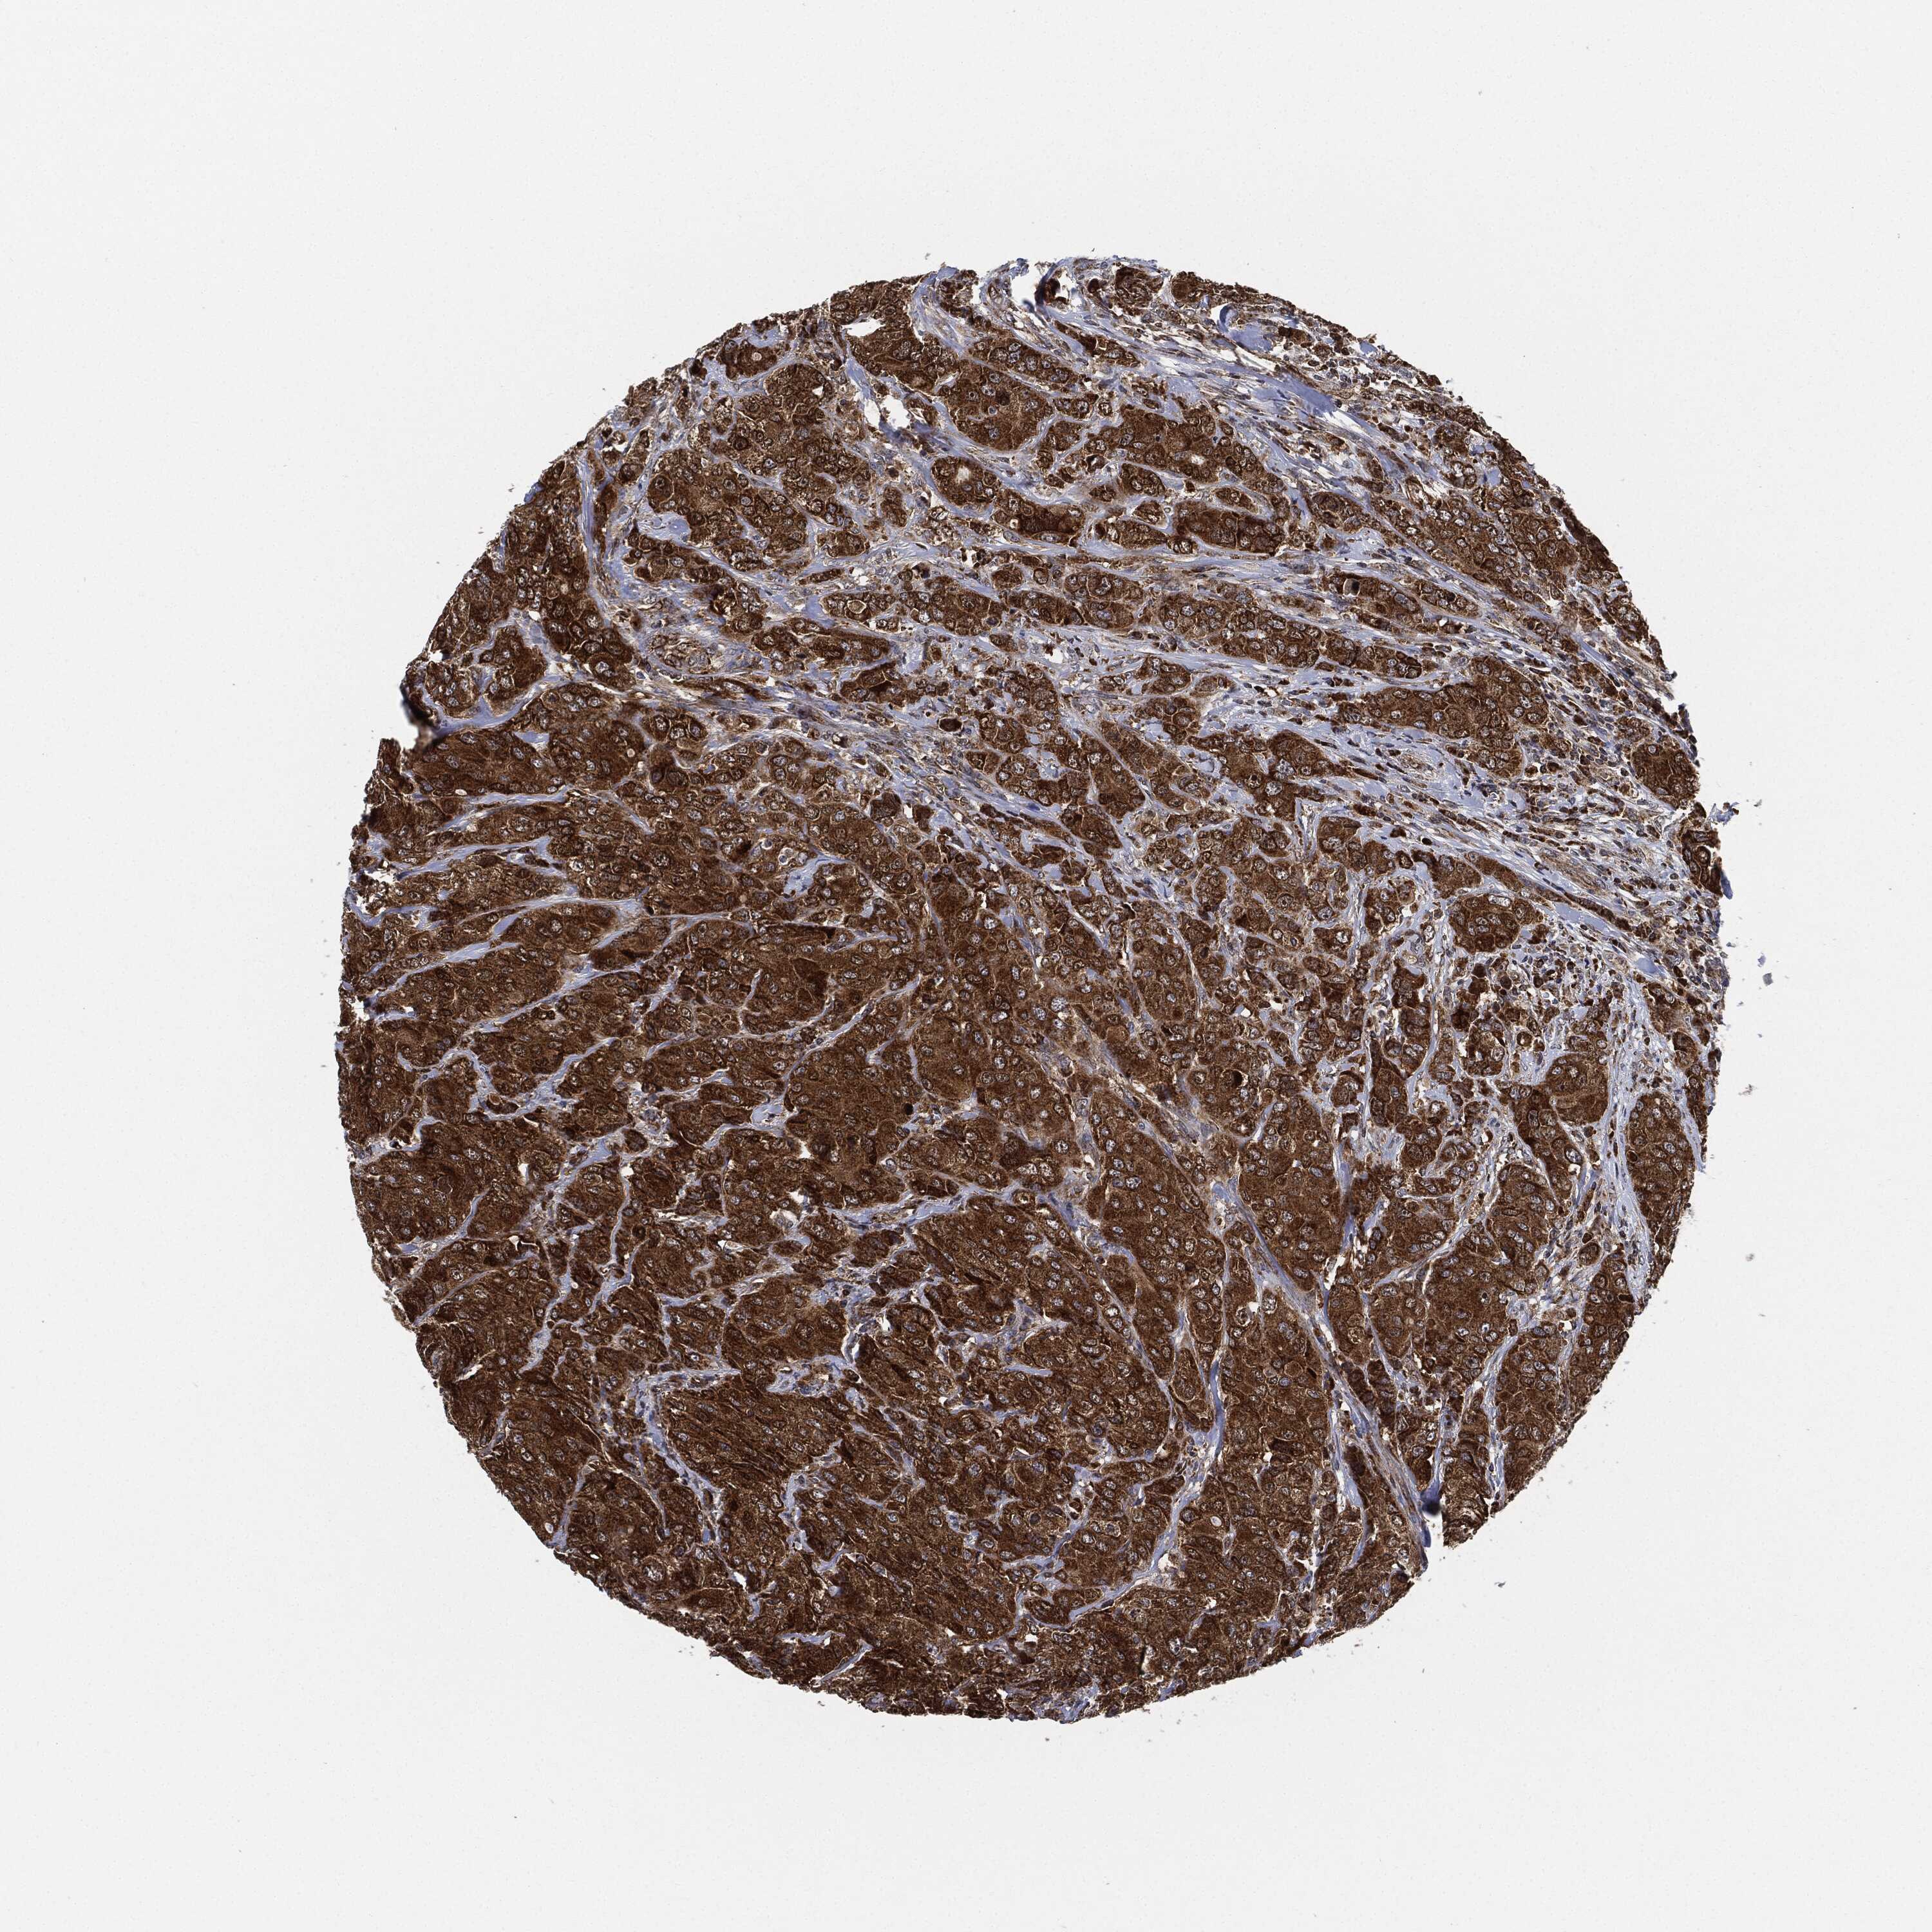

CANCER BREAST CANCER Show tissue menu

BRCA TCGA BRCA VALIDATION PROTEIN EXPRESSION